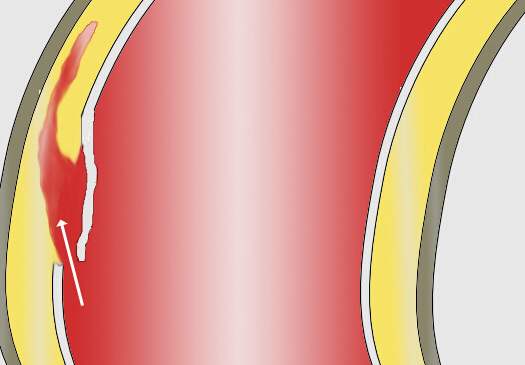

咱们再聊聊主动脉夹层这个病。主动脉夹层是血管撕裂性疾病,指的是人体最大的血管主动脉内膜破裂,血流在经过破口的时候进入中膜,形成真假两腔,类似于双层水杯,类似于轮胎鼓包,这样的一种疾病。死亡风险极其高,多数病人有突发的胸痛,也可以各种症状出现,临床迷惑性极强。

因此,既然是血管内膜的破裂,由于血管的生理保护机制,血小板就会出现聚集进行止血,凝血系统也会被激活参与止血,形成血凝块,只是这种血凝块发生在我们的大血管上,跟我们的手磕破了发生的过程一样。而体内另一个系统——纤溶系统为了对抗凝血也会分解掉一部分血栓变成D-二聚体产生抗凝的效果,只是效果比较弱而已,于是,凝血与血栓分解就这样动态平衡着,直到某一方战胜另一方(出血、凝血、纤溶三者动态平衡相互制约)。